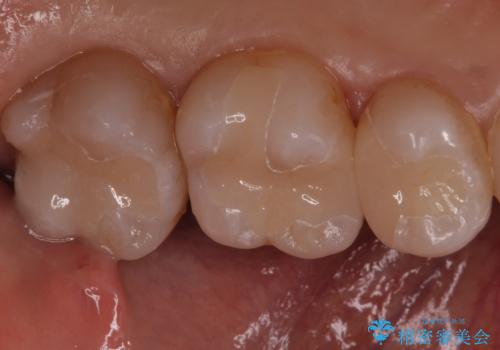

銀歯を白くしたい セラミックインレーでのやり替え

- 左上567 セラミックインレー:77,000円×3本費用は治療当時の料金となります

大きな虫歯さえなければ、銀歯のやり替えは詰め物の周りの歯を保存しつつ修復することができます。